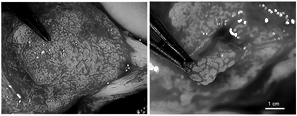

▲高清镜头下的手术操作

▲手术取精中

手术开始仅15分钟,许蓬院长便凭借精湛娴熟的技术成功获取了样本。样本被火速送至实验室后,李宏图副院长在短短五分钟内就锁定了活动精子。